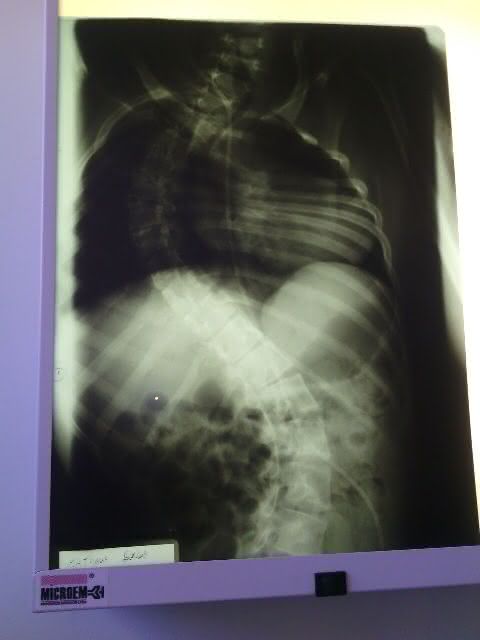

A equipe do portal visitou a residência do vigilante e da professoram que dedicam suas vidas ao pequeno Mateus Domingos dos Santos de 15 anos, que sofre de escoliose que é o encurvamento anormal da coluna vertebral, que provoca dor lombar e nas costas e pode morre caso não consiga realizar uma cirurgia nos próximos meses.

- Raio -X da coluna